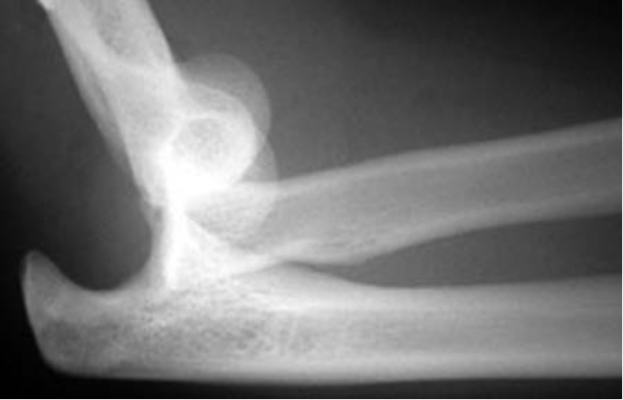

- Trật khớp đơn giản được phân loại thành ra trước hoặc ra sau. Trật khớp sau là phổ biến nhất (Mezera và Hotchkiss 2001) (Hình 3) và được chia tiếp nhỏ hơn theo hướng của xương trụ bị trật (sau, sau trong, sau ngoài, thẳng ngoài).